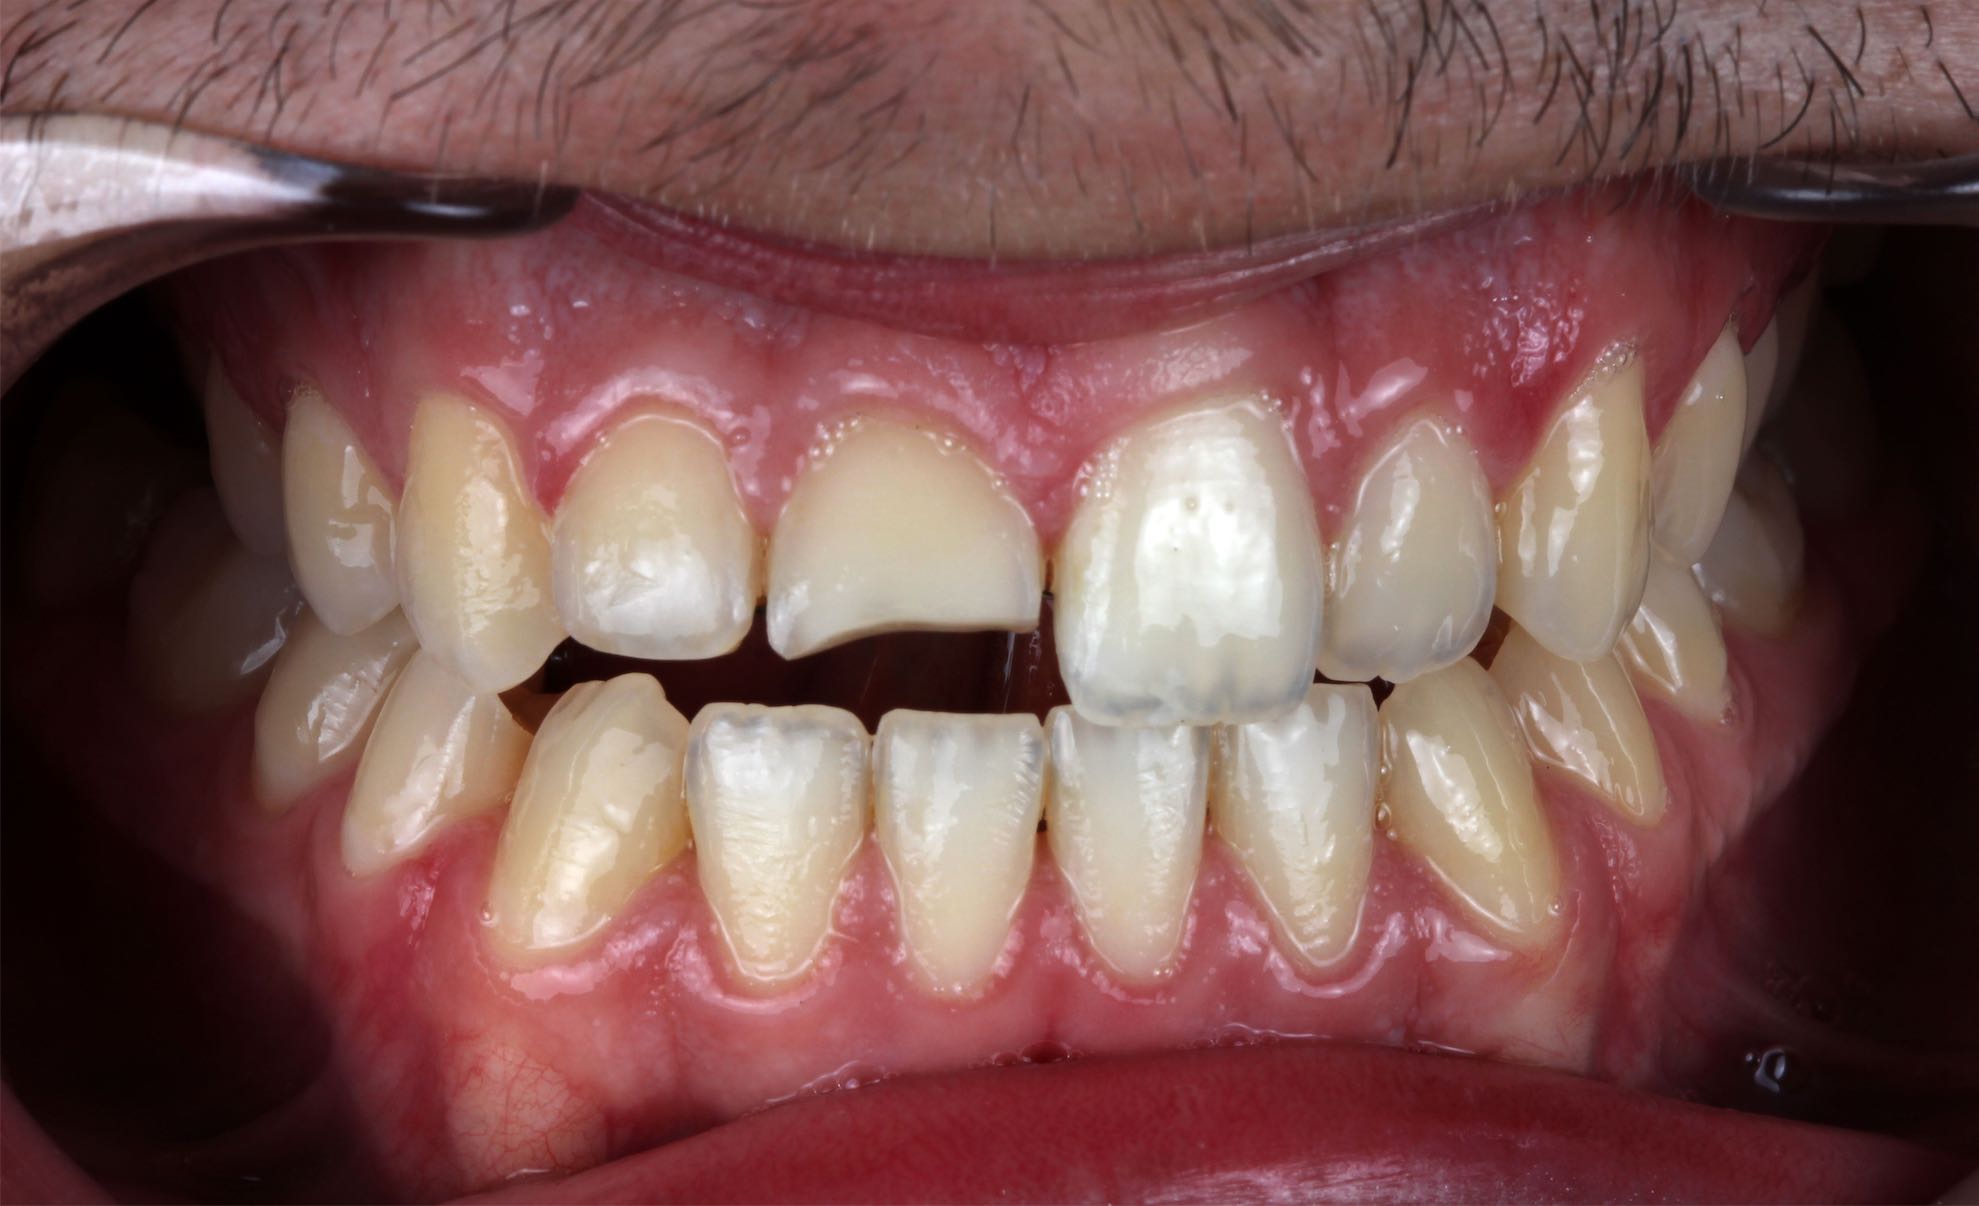

Odontología Estética. Coronas

BeforeAfter